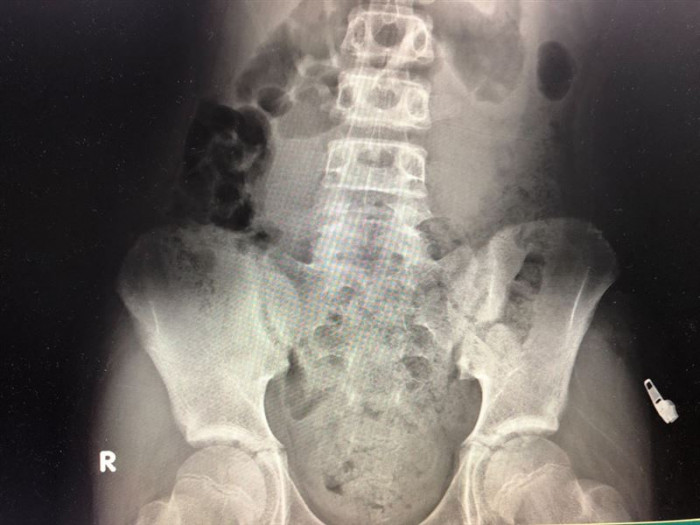

Sau khi chụp X-quang, bác sĩ phát hiện ruột của bé trai này chứa đầy phân. Cũng trong ngày hôm đó, bác sĩ Ngô tiếp nhận 3 trường hợp tương tự.

Ruột cậu bé chứa đầy phân.